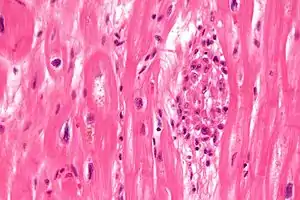

| Aschoff bodies are microscopic structures seen in patient with rheumatic fever | |

Microscopically, Aschoff bodies are areas of inflammation of the connective tissue of the heart, or focal interstitial inflammation. Fully developed Aschoff bodies are granulomatous structures consisting of fibrinoid change, lymphocytic infiltration, occasional plasma cells, and characteristically abnormal macrophages surrounding necrotic centres. Some of these macrophages may fuse to form multinucleated giant cells. Others may become Anitschkow cells or "caterpillar cells," so named because of the appearance of their chromatin.

The Aschoff nodules are foci of T lymphocytes, occasional plasma cells, and activated macrophages (Anitschkow cells) pathognomonic of rheumatic fever. These macrophages have abundant cytoplasm and central round nuclei in which chromatin condenses into a central, slender, wavy ribbon, reason why they are sometimes called "caterpillar cells". They are especially found in the vicinity of small blood vessels in the myocardium and endocardium and occasionally in the pericardium, and also the adventitia of the proximal part of the aorta. Lesions similar to the Aschoff nodules may also be found in extra-cardiac tissues.